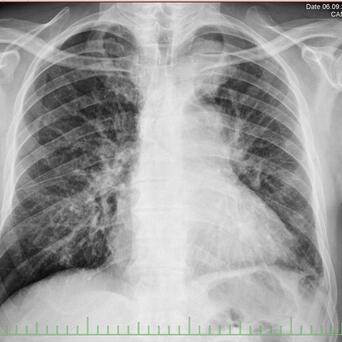

等到细胞变化积累到一定程度,就进入了癌前病变的阶段。这已经是临床上可以检测到的结构改变了。

比如胃黏膜的肠上皮化生、宫颈的上皮内瘤变、结肠的腺瘤性息肉,这些在胃镜、宫颈涂片、肠镜检查中都能发现。

癌前病变不等于癌症,但它意味着风险已经实实在在地升高了。以结肠腺瘤为例,直径超过一厘米的腺瘤如果不干预,十年内有将近百分之二十四的概率发展为结肠癌。